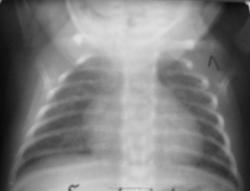

Недоношенный 34 недели находится в стационаре с диагнозом Синдром дыхат.расстройств.На ЭХО: ДМЖП, ОАП, ООО, сброс слева направо.3 снимка.Между 1 и2 сн. 6 дней,. между 2 и3 сн. 10 дней.3 и 4 сн. один и тот же,лучше сфотограф.не получается.На последнем снимке признаки лег.гипертензии за счет ВПС или воспаление? Динамика?

Убедительных данных за пневмонию нет.

Из-за разного качества снимков судить о динамике сложно, но помоему она есть, позитивная. Пневмонию тоже не вижу. Признаки гипертензии, отека, РДС у деток малоспецифичны. А гидроперикарда на ЭХО не было?

"Слегка" опоздал к началу обсужденияsad.  ИМХО: легкие без очаговых и инфильтративыных изменений( норма). Сердце:" круглое"( вероятно порок, но это переготива эхокардиографии).Сообщите пожалуста,какой окончательный диагноз будет у пациента!

Всем большое спасибо!Я тоже думаю,что за счет разной глубины вдоха, сгущение рисунка на 3 снимке.Клинически на данный момент все нормально.При переводе из род.дома была одышка,цианоз носогуб.треугольника.3-е УЗИ во время берем-ти не делала,поэтому ВПС был новостью для мамы.Перикардита на ЭХО нет.Готовится к выписке домой.